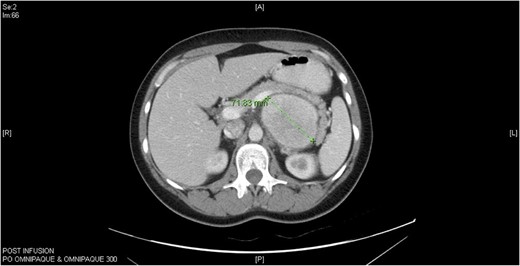

A 33-year-old Caucasian female with an unremarkable medical history and vague abdominal discomfort presented with a retroperitoneal peripancreatic mass on ultrasound. A triple-phase intravenous contrast computed tomography (CT) confirmed an inhomogeneous lesion (>7 cm) displacing the stomach and distal pancreas (Fig. 1). Endoscopic ultrasound-guided fine needle aspiration biopsy (EUS-FNA) showed polymorphic lymphocytes and penetrating capillaries. Two months later, a second EUS-FNA revealed the mass had increased in size; the biopsy was negative for malignancy. Resection was indicated due to the patient’s young age and the difficulty of obtaining definitive diagnosis.

Computed tomography (CT) abdomen horizontal section of Castleman’s disease in accessory spleen.